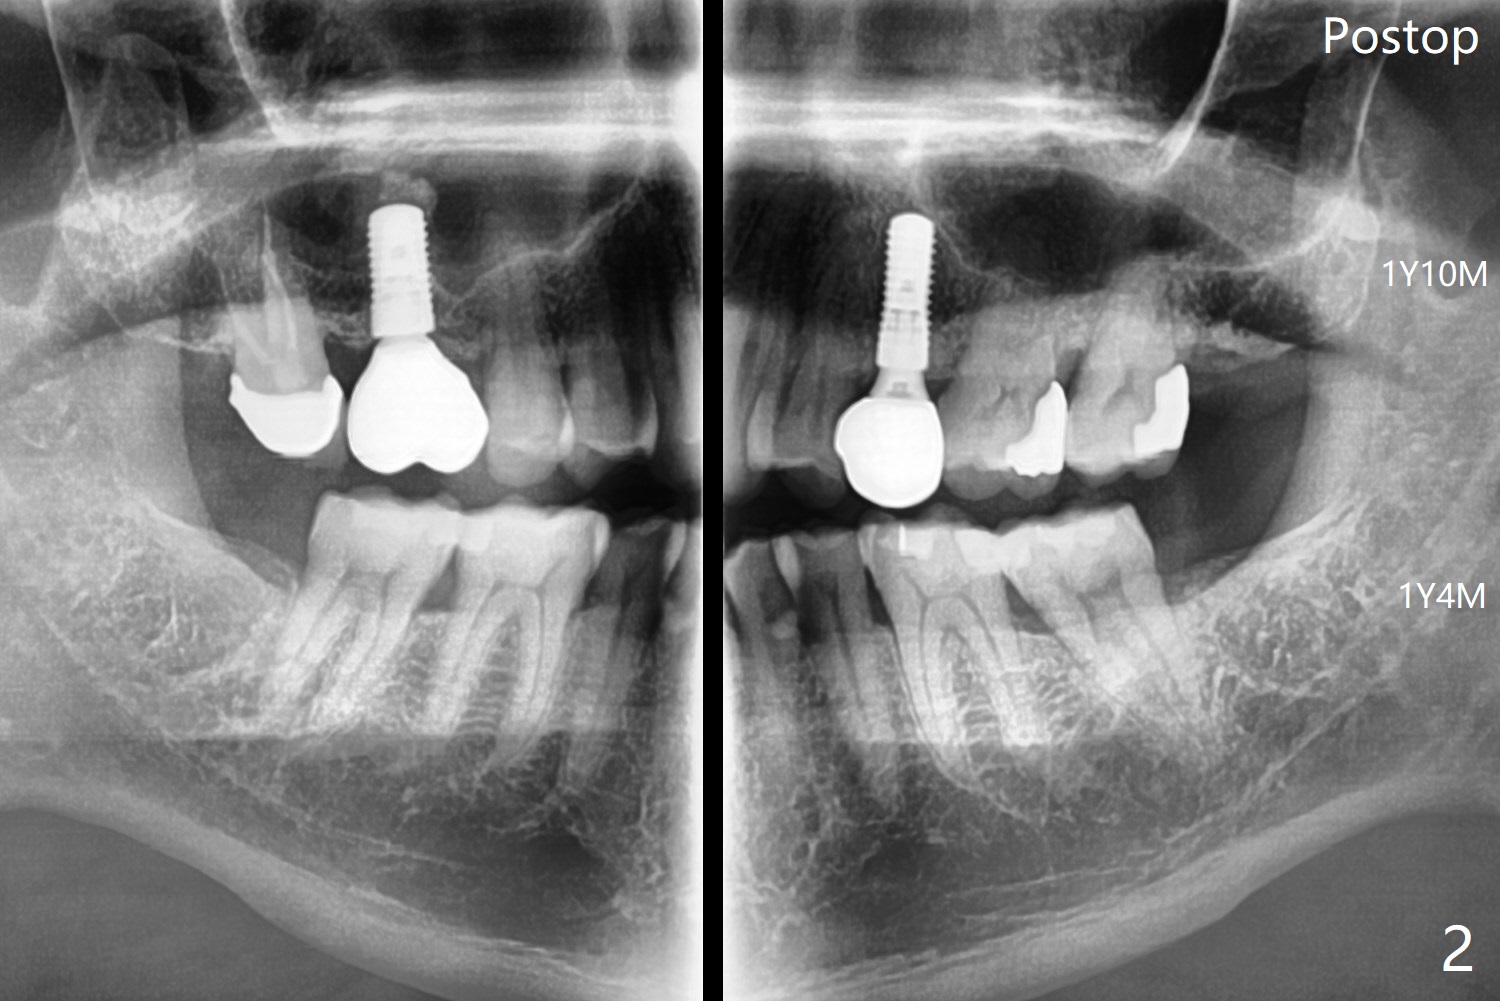

61岁男在拔除左上智齿后5个月拔除左下智齿(图一,最有可能使用Osteogen Plug),术后愈合正常(图二)。